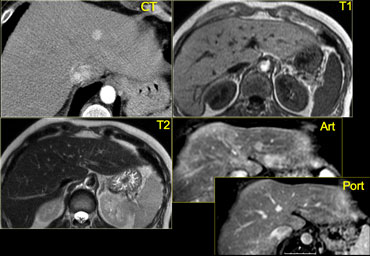

Left-lobe fibrolamellar HCC. Courtesy Dr. Federle and Dr. Ichikawa (3) Left-lobe fibrolamellar HCC. Courtesy Dr. Federle and Dr. Ichikawa (3)

Fibrolamellar HCC (3)

On the left CT- and MR-images of a left-lobe fibrolamellar HCC in a 19-year-old man.

A. Non-enhanced transverse CT scan shows calcification (curved arrow) within the hypoattenuating tumor (straight arrows).

B. Hepatic arterial contrast-enhanced transverse CT scan shows heterogeneous hypervascularity within the tumor (arrows).

C. Ten-minute delayed transverse CT scan demonstrates subtle areas of hyperattenuation that represent fibrous tissue within the central scar, radiating septa, and capsule (open arrows).

Curved arrow = calcification.

D. Transverse T2-weighted MR image (5,000/105) also demonstrates the central scar and septa (open arrow).

The tumor itself (straight arrows) is nearly isointense to liver (the only such case in our series).